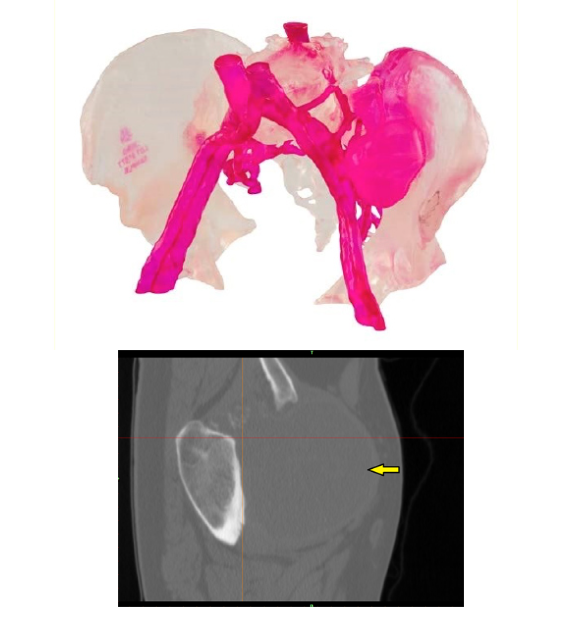

△使用3D打印假体修复因癌症而受损的骨盆

产品中包括针对患者的植入物,以及用于髋臼重建和跨越骨盆多个区域的高级重建。植入物的设计和打印具有独特的功能,有助于解决骨骼和软组织附着,以及解剖修复准确性的挑战。